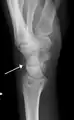

Triquetral fracture indicated by the white arrow.

Triquetral fracture as seen on lateral view of a radiograph.

Triquetral fractures can occur due to forceful flexion of the wrist, causing an avulsion of the dorsal aspect of the bone that is often hidden on anterior radiographs, but can be seen as a tiny bone fragment on lateral views.